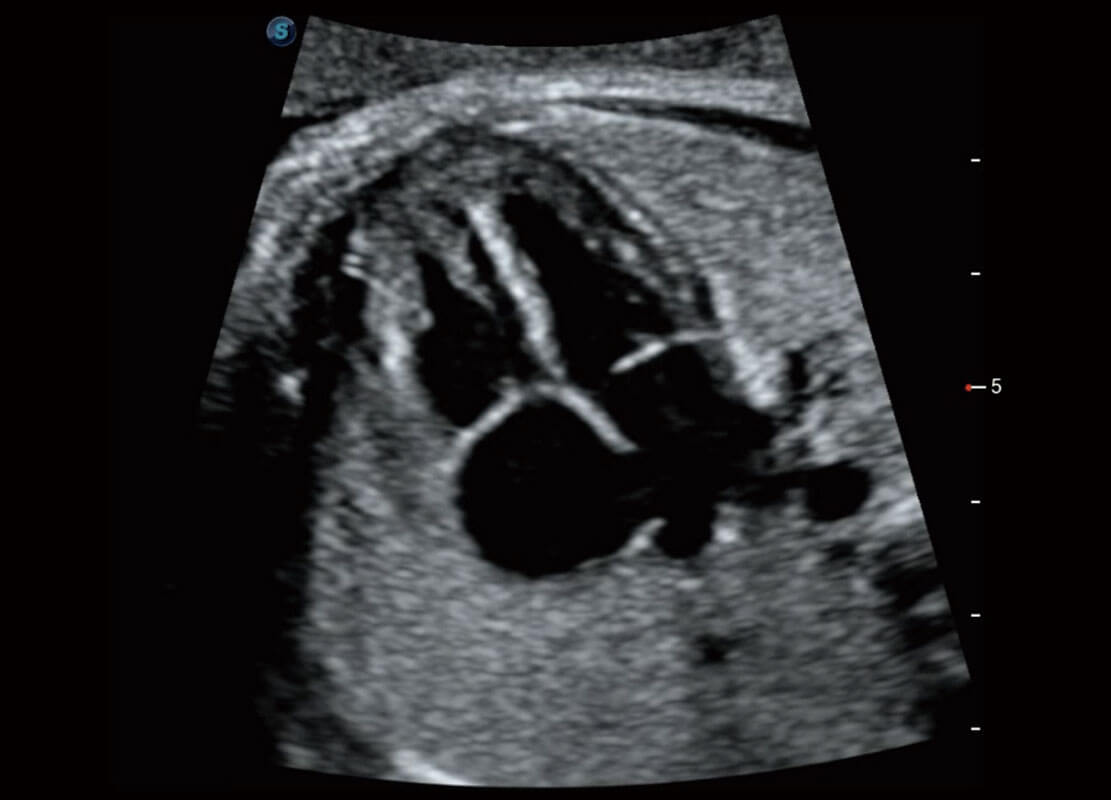

P60为盆底超声检查提供应用方案,多种腔内及腹部容积探头提供从二维、三维到四维的优异图像品质,实时快速三维容积数据获取,专业的测量工具包等人性化设计,为超声医生诊断提供有力保障。

Lev.Hiat A-r: 16.33 cm2

Lev.Hiat H-r: 53.70 mm

Lev.Hiat W-r: 43.96 mm

Lt-LUG-r: 24.16 mm

Rt-LUG-r: 19.94 mm

能够简化盆底检查的操作流程,可在二维模式及三维成像模式下实现一键自动提取出标准切面、自动识别当前切面、自动测量,提升盆底检查的高效性,同时也能让青年医生快捷的获得准确的检查结果。